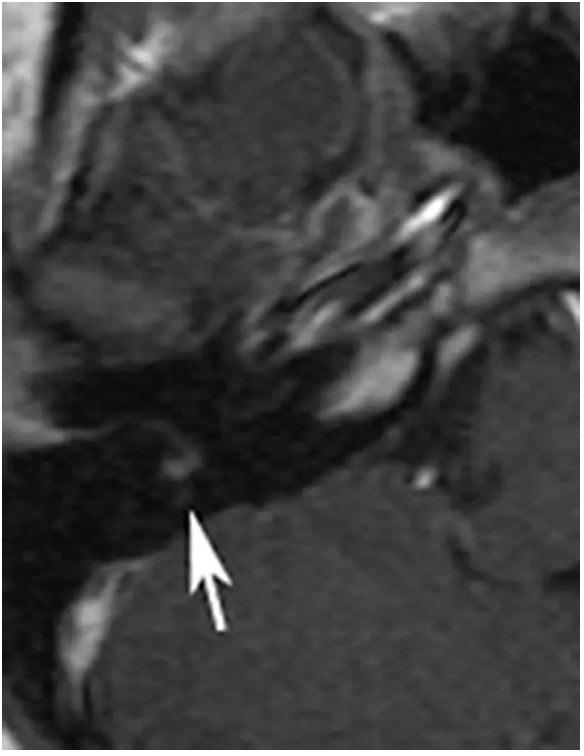

A 23-year-old woman is evaluated because of Bell palsy. An MR image with contrast of the facial nerve is shown. The arrow corresponds to which of the following segments of the facial nerve?

A. Labyrinthine segment

B. Meatal (canalicular) segment

C. Tympanic segment

D. Mastoid segment

E. Extratemporal segment

A

Correct Answer: Mastoid segment